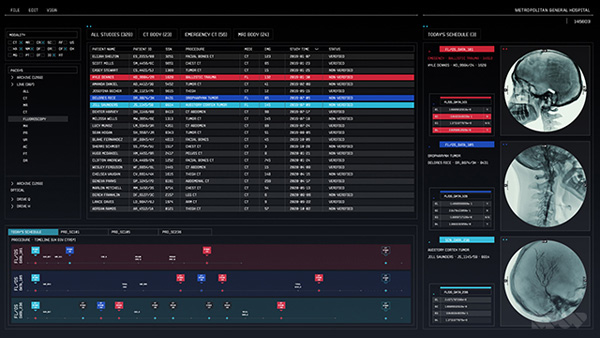

The art department also supplied them with a lot of the reference they needed for looks – ultrasound output, X-ray images and MRI scans. SPOV sourced some PACS screens as well, as samples of the standard Picture Archiving and Communication System that medical staff use to compile databases of all kinds of data.

Achieving the authenticity required in their brief meant following through on all details in a genuine way, so that everything fit in and would satisfy the fans and geeks. The small details, colours, textures, views and bits of text aren’t added gratuitously for effect, but appear as they would on real imagery for screens in a hospital. “Actually, we had a secret advantage in that our former studio manager at that time was preparing to be a nurse. She would look over our work and tell us what looked out of place or was missing – just what we needed to help sell the images,” said Allen

Deliverables were determined by the fact that the images were not composited into plates as elements for VFX shots. Instead, they were played back on set inside the monitoring devices and consoles used as props, and shot as part of the plate. On-set supervisor Mark Jordan from Compuhire Computer & Video Playback organised the playback. “Because we have worked with Mark’s team before on similar projects, we knew how to set up the workflow to output the formats they need - a mixture of QuickTime movies, image sequences supplied as tiffs and/or gifs, and stills. Their remit is making our files function on set as required by the director - our part is making it look convincing and move in a believable manner.”

Looking authentic and attractive in isolation is one thing, but Allen is especially pleased with the way the images look in the movie – not just on darkened sets where they glow against a black background but also in fully lit scenes where they integrate completely into the everyday world of the hospital. “Cinema 4D’s tools don’t get in the way of the creative process," he reflected. "It helps us quickly identify the most efficient route to achieve the result we’re seeking – from revolutionary flying vehicles or fantastic game characters, to something as real as an X-ray or MRI scan – and to cut down on iteration time.” www.spov.tv